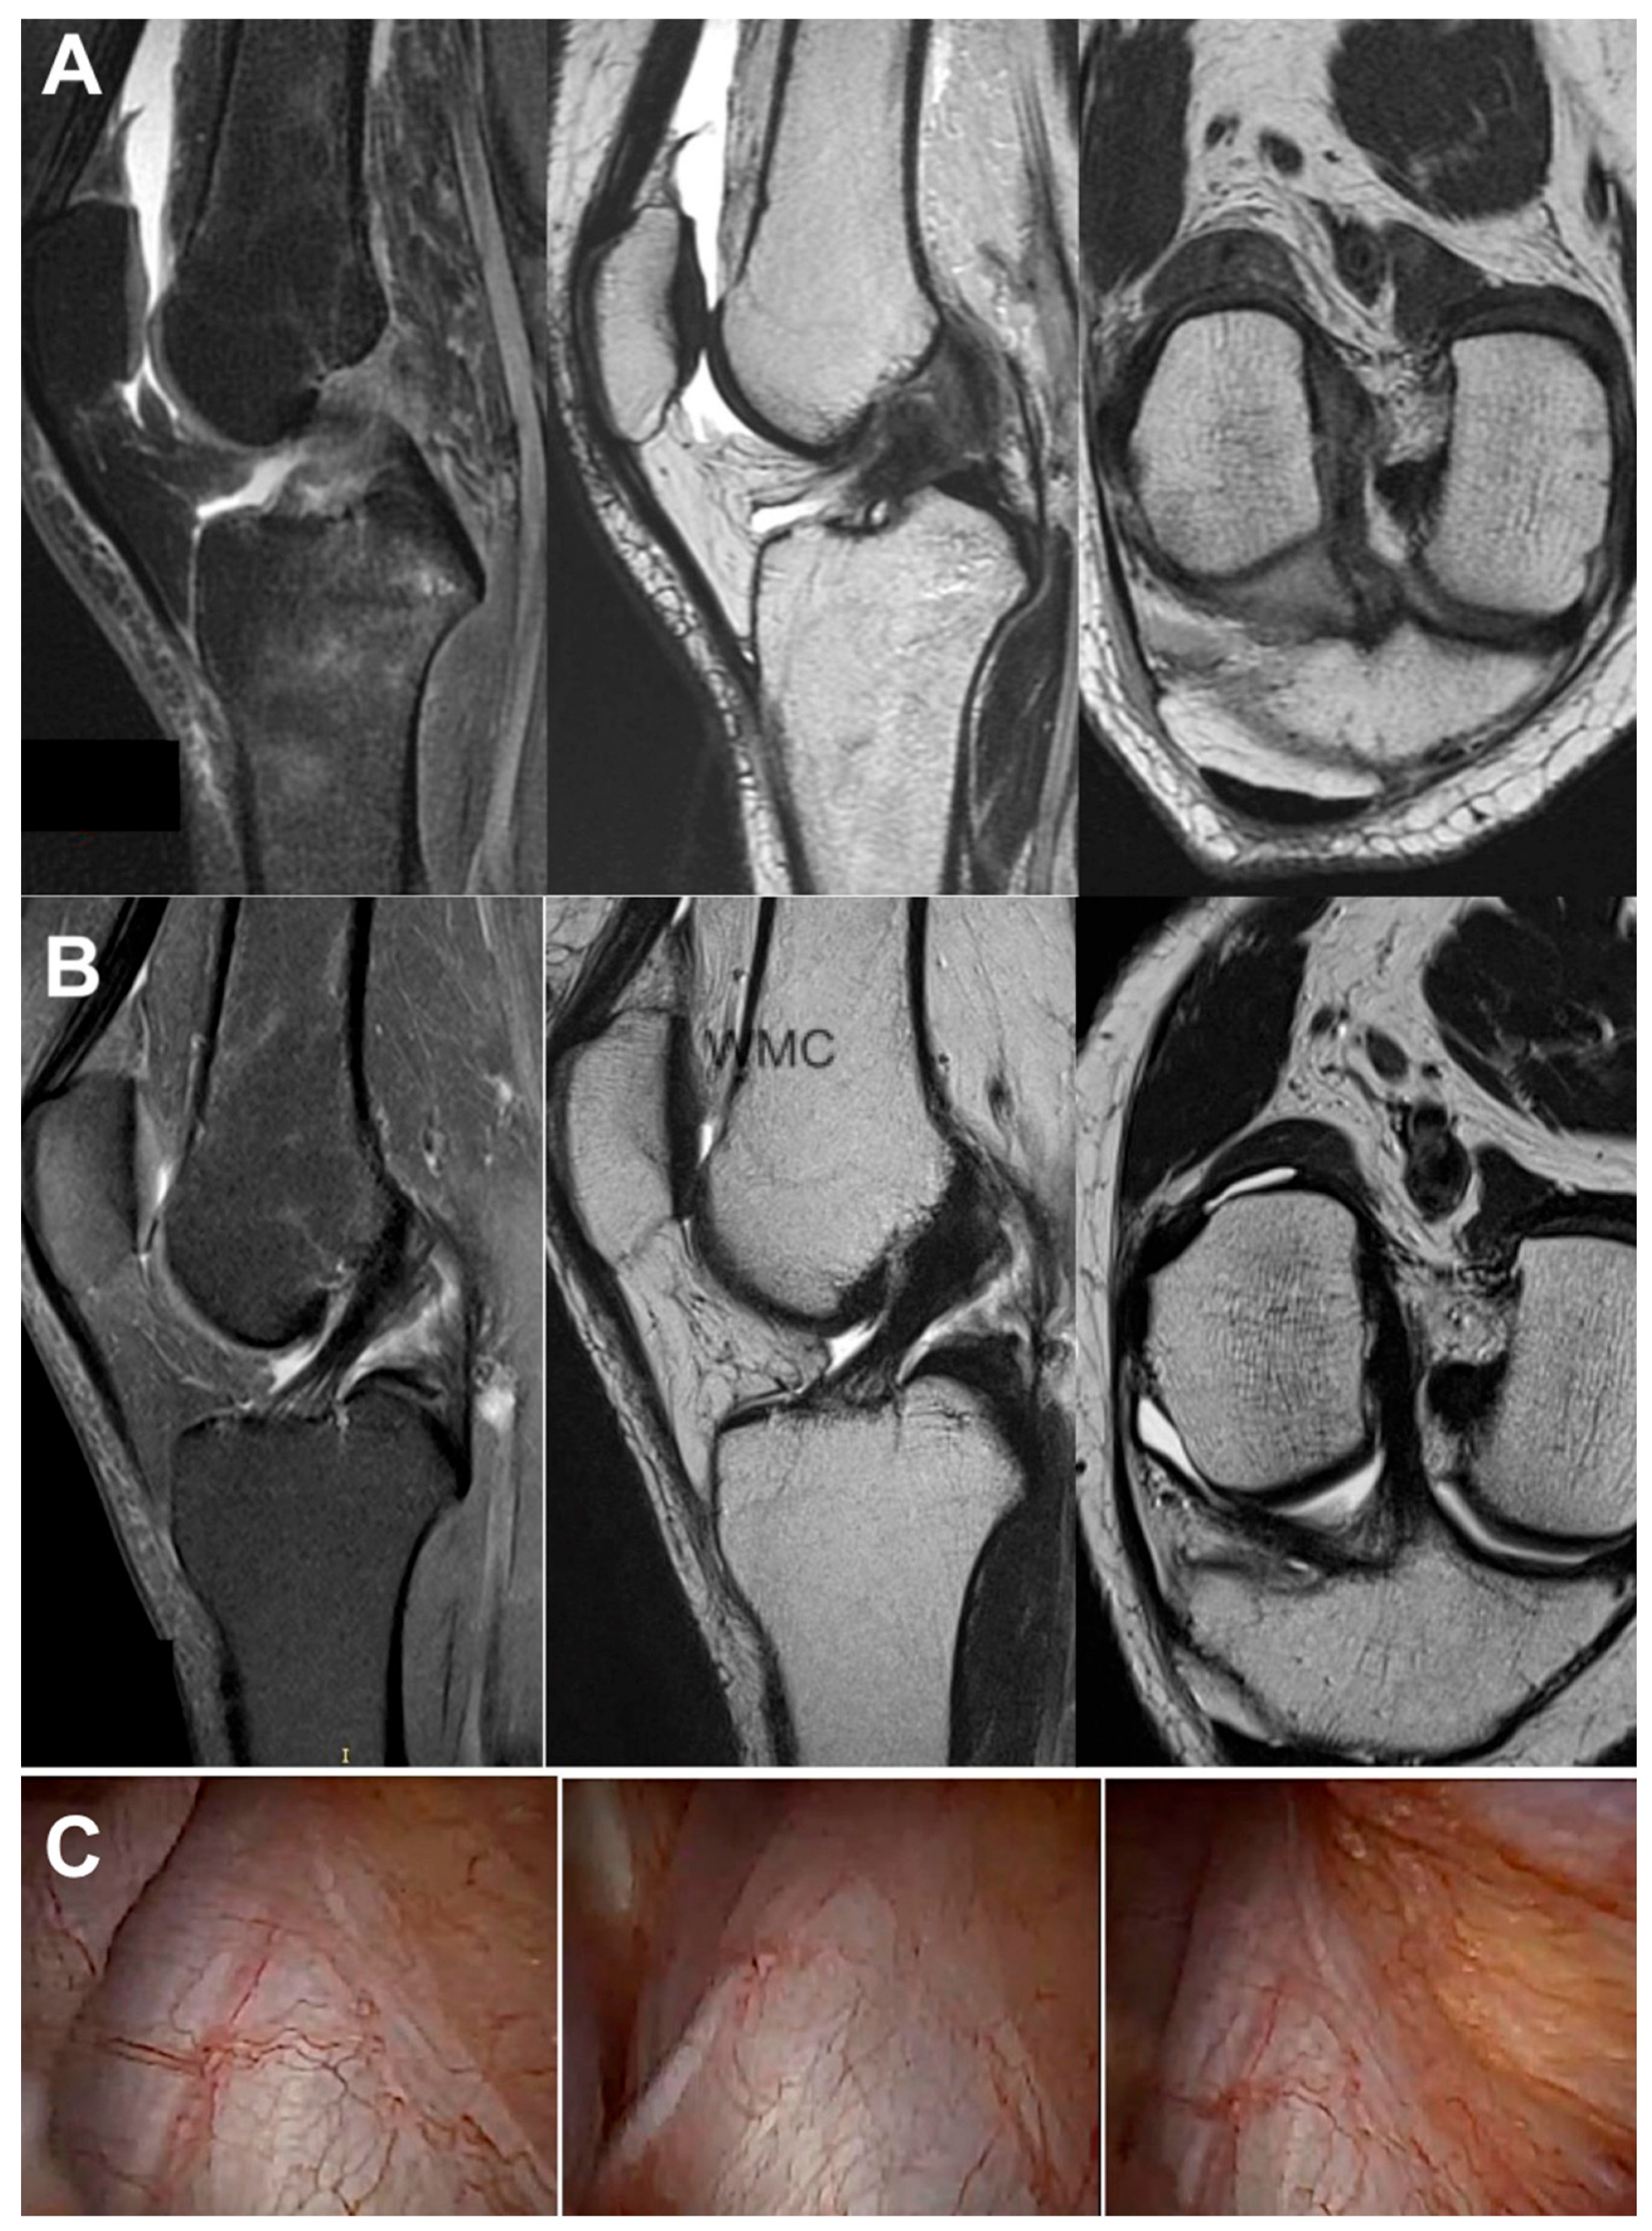

3.3. Imaging Analysis